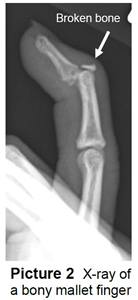

• It can sometimes break off a piece of bone. This is called a bony mallet (Picture 2). If the bone doesn’t break but the tendon tears, it’s called a soft tissue mallet.

Your child’s doctor or health care provider will ask what happened, examine the finger, and take an X-ray to see if the bone is broken.